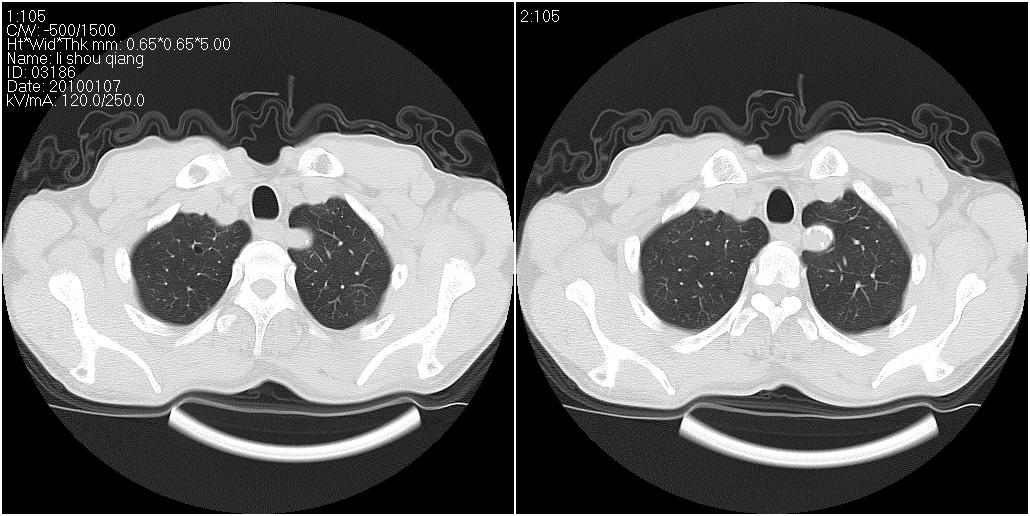

右肺中叶外侧段见一不规则的软组织肿块,边缘可见毛刺,并见厚壁空洞,与胸膜分界欠清。另左下肺见多个小囊状扩张区

右肺中叶外侧段可见团块影,外形不规则,内见空泡征。左下肺见蜂窝状低密度透亮影,部分层面主动脉旁瘤样突出。考虑右肺中叶外围型肺癌可能性大,左下肺支气管扩张,主动脉弓瘤样突出。